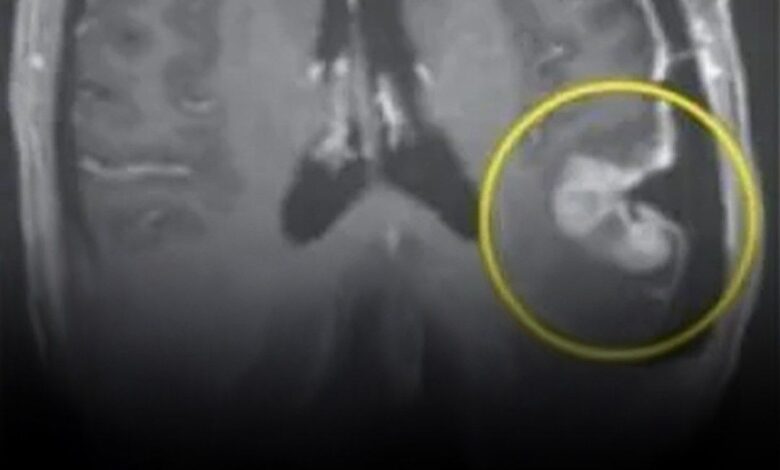

The clinical response was immediate and, in the words of the investigators, “stunned” the medical community. The trial involved three patients with recurrent glioblastoma—cases where all other treatments had failed. In the first patient, a 72-year-old man, the tumor shrank by 18.5% within just two days of a single infusion. By the tenth week, the tumor had regressed by over 60%. The second patient, a 57-year-old woman, saw her tumor nearly disappear on MRI scans within five days. The third patient, a 74-year-old man, showed similar rapid regression in a timeframe previously thought impossible for a biological therapy.